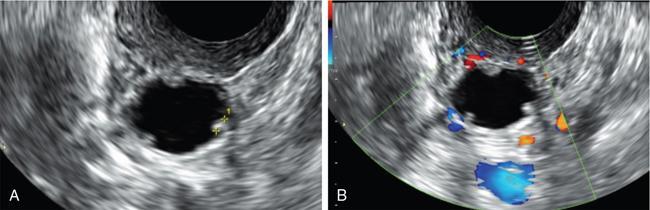

John De Lindsay, Subhashree C SALPINGITIS Salpingitis refers to the diffuse inflammation of the fallopian tubes and can be unilateral or bilateral. It is the most common early form of PID. Salpingitis has the highest risk of infertility and ectopic pregnancies. Coexisting endometritis can be seen in up to 70%–90% of nonobstetric patients. The clinical presentation in salpingitis can be variable, from being asymptomatic to severe pelvic discomfort and tenderness. Poor correlation is often noted between the degree of symptoms and the extent of tubal inflammation. In salpingitis, the fallopian tubes become hyperemic and swollen due to inflammation. With suppurative salpingitis, the lumen of the tube distends with pus and spills over into the peritoneal cavity, coating the serosa of the adjacent uterus and ovary. US maybe used as the first-line imaging modality for evaluating suspected salpingitis. Subtle abnormalities such as fallopian tubal tenderness with tortuosity, increased wall vascularity and tubal thickening of more than 5 mm may be considered pointers towards salpingitis. Salpingitis may be considered on CT when the fallopian tube thickening is more than 5 mm in axial dimension with enhancing walls (Fig. 11.17.1.1). Adjacent peritubal free fluid or cul-de-sac fluid may be other indicators. Fallopian tube thickening is the most specific sign to arrive at a diagnosis of salpingitis (Fig. 11.17.1.1). Chronic salpingitis may present as diffuse tubal irregularity with narrowing or complete obliteration of the tubes. Salpingitis isthmica nodosa is a benign inflammatory process causing nodular scarring of the fallopian tubes. At hysterosalpingography, tubal irregularity and subcentimetric protrusions from the isthmic portion of the tube are seen. PELVIC INFLAMMATORY DISEASE Pelvic infection is one of the most frequent cause of pelvic pain in females. Diagnosis of pelvic inflammatory disease (PID) can be challenging because it mimics other abdominal and pelvic processes. Pelvic ultrasonography is the first line investigation of choice. Multimodality imaging with CT and MRI are required for making a definitive diagnosis and for assessing the extent of disease and complications. PID is a spectrum of disease where microorganisms cause an inflammatory continuum ascending from the lower genital tract to infect the uterus, fallopian tubes, ovaries and may extend to the peritoneal cavity. The infection begins with cervicitis and progresses to endometritis, salpingitis, pyosalpinx, tubo-ovarian complex and ultimately tubo-ovarian abscess (TOA) (Fig. 11.17.2.1). One-third to one-half of cases are due to chlamydia trachomatis or Neisseria gonorrhoeae. However, PID is most commonly (30%–40%) a polymicrobial infection and substantial proportion of cases are nongonococcal and nonchlamydial in origin. It may be due to vaginal flora, anaerobic gram-negative rods and Mycoplasma bacteria. Tuberculosis and actinomycosis occur less frequently. Risk factors for PID include young age, multiple sexual partners, an increased frequency of coitus and the presence of intrauterine contraceptive device. Secondary infection of adnexa from gastrointestinal origin like appendicitis and diverticulitis is also common. Clinical diagnosis of acute PID often presents a challenge due to overlap of symptoms and signs with conditions like endometriosis, appendicitis and ectopic pregnancy. Symptoms: Pelvic pain is the most common symptom, although may be absent or mild in some patients. Mucopurulent vaginal discharge and fever are the other usual symptoms. Signs: Per vaginal examination reveals cervical motion tenderness, uterine and adnexal tenderness. Chronic PID symptoms: Patients may be asymptomatic. They can present with chronic pelvic pain, low back ache, dyspareunia, abnormal vaginal bleeding and vaginal discharge. WBCs on saline microscopy of vaginal secretions, elevated ESR, CRP and leucocytosis. A delay in treatment of PID causes significant reproductive and gynaecologic morbidity, such as infertility, increased risk of ectopic pregnancy, chronic pelvic pain and recurrent infection. Hence there is need for proper and adequate treatment of this condition. Most patients can be treated as out-patients with broad spectrum antibiotics. Hospitalisation is required in severe cases like TOA (Fig. 11.17.2.2). Inflammation of uterine cervix. May be infectious or noninfectious. Infectious cervicitis represents early presentation of PID. USG shows an enlarged cervix and hyperaemic cervical canal. CT and MRI show an enhancing endocervical canal. Cysts can be seen lining the endocervical canal. Cervical stroma is usually intact. Differentiation from cervical malignancy is made by lack of enhancing solid components in the abnormal cervix. Inflammation of the endometrial lining of uterus. Usually occurs during pregnancy or postpartum state or gynaecologic instrumentation. USG imaging findings depend on stage of PID. In early or mild infection, the findings are nonspecific. Endometritis may not exhibit any sonographic findings. A fluid-filled endometrial cavity is suggestive of endometritis in the setting of fever, vaginal discharge and uterine tenderness on physical examination. Intrauterine fluid is a nonspecific finding. Gas in the endometrial cavity will appear as foci of increased echogenicity with posterior dirty shadowing. Presence of gas increases the possibility of infection, though gas in the endometrial cavity can be present postpartum and postinstrumentation. Fluid in cul-de-sac is again a nonspecific finding. Internal echoes within the fluid could suggest infection (or haemorrhage) (Fig. 11.17.2.3A).